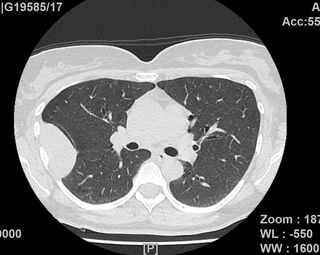

Lungenkrebs

Lungenkrebs befällt etwa 25 Prozent aller Krebskranken und gilt als häufigster Tumor beim Mann. Doch auch immer mehr Frauen sind betroffen. Die chirurgische Therapie ist für uns Mittel der Wahl, sofern keine Fernmetastasen vorhanden sind. Dabei können wir in unserer Klinik technisch hoch anspruchsvolle Lungenoperationen auf endoskopische Weise videoassistiert vorgenommen werden.

Lungenmetastasen

Werden neben Lungenkrebs auch Lungenmetastasen diagnostiziert, stellt das die Medizin vor höchste Herausforderungen. Nur wenige Kliniken sind darauf spezialisiert, bei dieser Erkrankung chirurgisch einzugreifen. Durch besondere fachliche Expertise, einen großen Erfahrungsschatz und die technische Ausstattung ist unsere Klinik Ihr Ansprechpartner, wenn es um die chirurgische Therapie von Lungenmetastasen geht.

Laser-Chirurgie bei Lungenmetastasen

In unserer Klinik für Thoraxchirurgie werden zahlreiche Operationen an der Lunge mit dem modernen 1318NM-Diodenlaser durchgeführt. Das neue Gerät wurde speziell für die Lungenchirurgie entwickelt und hat besondere Eigenschaften, die das Schneiden von Lungengewebe ermöglichen: Mit dem Laser ist der Thoraxchirurg in der Lage, bluttrocken und übersichtlich durch das Lungengewebe zu schneiden. Dadurch können Metastasen und Tumoren, die tief im Lungengewebe liegen, onkologisch sicher entfernt werden. Anhand dieses modernen Verfahrens kann der Thoraxchirurg besonders gewebeschonend vorgehen und zahlreiche Lungenmetastasen entfernen, was mit konventionellen Methoden nicht möglich wäre. So kann die Prognose für den Patienten verbessert werden. Die sogenannte Laser-Metastasektomie ist eine etablierte chirurgische Behandlung, die bundesweit nur in großen Thoraxkliniken vorgenommen wird. Unsere Klinik ist die einzige in Ostwestfalen-Lippe, die Laser-Chirurgie bei Operationen der Lunge anbietet.

- Lungenrundherd (Lungenverschattung)